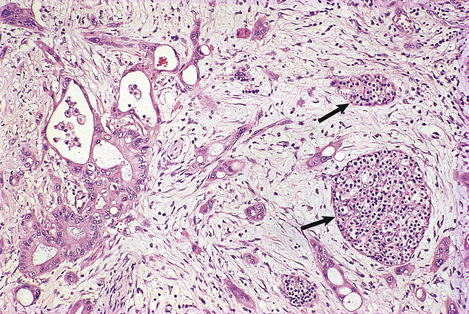

Primary biliary cirrhosis is misleadingly named because cirrhosis is a late manifestation of the disease and many patients have the condition diagnosed before this stage is reached.

The stages in the development of the disease are:

autoimmune destruction of bile duct epithelium, particularly that of the smaller intrahepatic ducts; histologically, the damaged ducts are surrounded by a dense lymphocytic infiltrate and granulomas are often present (Fig. 16.12)

later proliferation of small bile ductules, perhaps in a vain attempt to replace those that have been deleted by the autoimmune process

architectural disturbance due to portal and bridging fibrosis

cirrhosis.

image

Fig. 16.12 Histology of primary biliary cirrhosis. Lymphocytes surround a bile duct, the epithelium of which is damaged as a result of the autoimmune process.

Copper accumulates in the liver cells because it can no longer be adequately excreted in the bile.

In addition to the biopsy appearances, which may not be absolutely diagnostic in the later stages, other important features of primary biliary cirrhosis include:

elevated serum alkaline phosphatase and IgM levels

an anti-mitochondrial auto-antibody in the serum

pruritus, jaundice and xanthelasmas (yellow deposits of lipid-laden macrophages in the skin around the eyes).